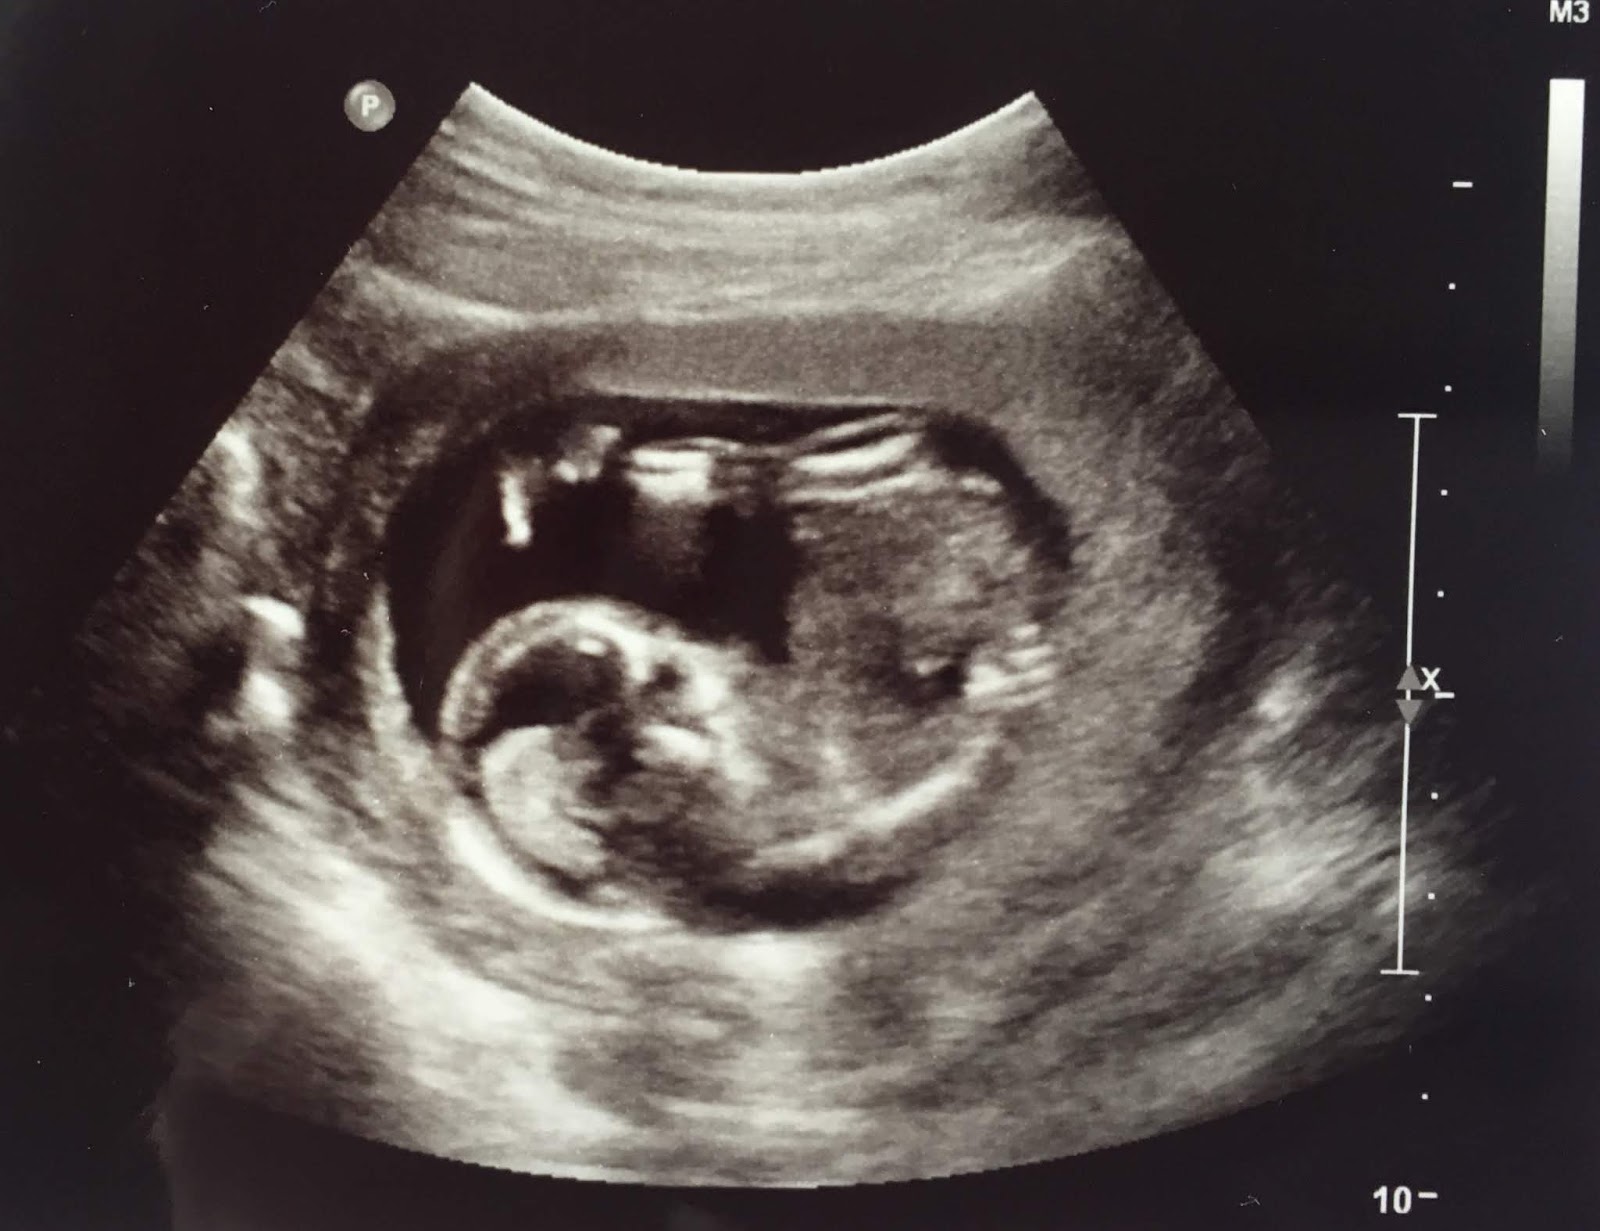

Baby Chris is Twelve Weeks Old

One-third of this pregnancy is over! Baby Chris has entered the second trimester, and this week, his or her weight has increased about 58%. He or she is now about the size of a lemon.

The bladder is developing smooth muscle cells, the taste buds are maturing, and the arms have lengthened. Fingernails and toenails are forming. Baby Chris’s nervous system is sensitive enough to respond to light touch in most places. Baby Chris can squint, frown, grimace, suck, and chew.